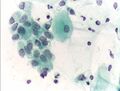

صورة مجهرية لاختبار عنق الرحم تُظهر آفة داخل الظهارة منخفضة الدرجة (LSIL) ومخاطية باطن عنق الرحم الحميد. صبغة عنق الرحم .